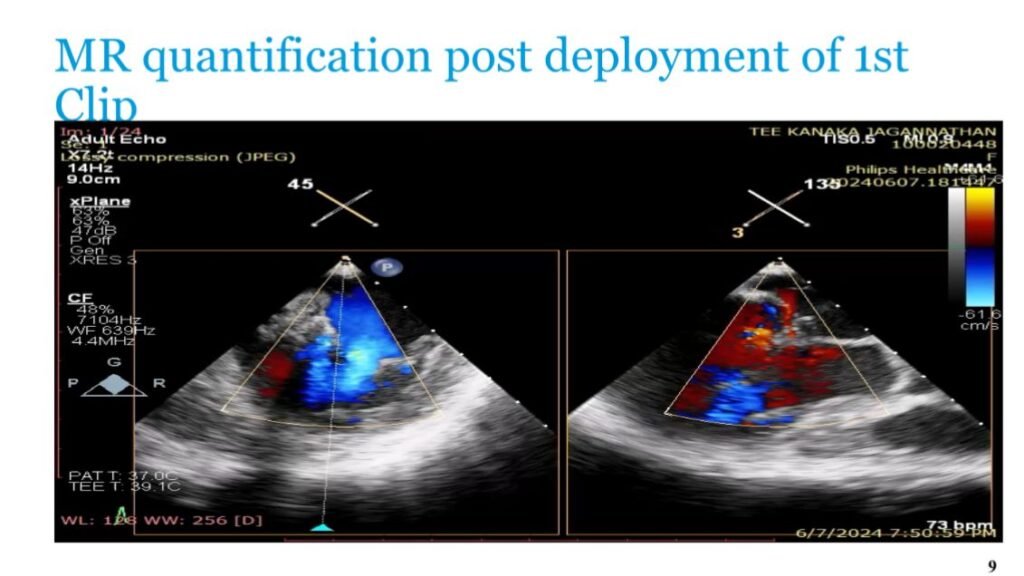

A multidisciplinary team led by Dr. Amit Bhushan, Director & Unit Head – Cardiology, Paras Health Gurugram, performed a rare, high‑risk dual intervention using MitraClip (TEER) to repair the severely leaking mitral valve and restore circulation.

“This was one of the most challenging cases we have managed. A single intervention alone could not have saved him. We deployed a second MitraClip, during which the patient went into shock and required CPR. After multiple episodes of instability, he was revived. The MitraClip repaired the leaking valve, restored forward blood flow, and stabilised the heart enough to support recovery. This coordinated, stepwise approach was the only viable path when every other option had been exhausted.”

TEER (Transcatheter Edge‑to‑Edge Repair) is a minimally invasive valve‑repair procedure performed through a vein in the leg. A small clip is attached to the leaking mitral valve to prevent backward blood flow, improving heart rhythm and pumping efficiency. It is often the only option for patients too high‑risk for open‑heart surgery.

The complex intervention involved 14 specialists, including interventional and non‑invasive cardiologists, cardiac anaesthesia, intensivists, cath‑lab teams, paramedical staff, and technical experts guiding the MitraClip under 3D TEE and fluoroscopy.